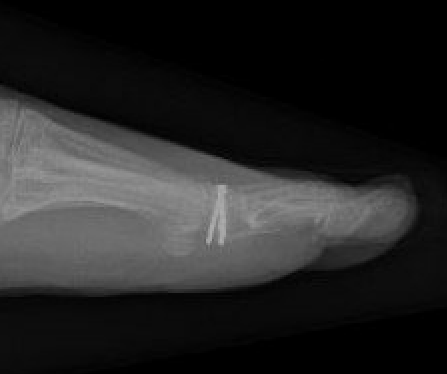

Weil Osteotomy

Technique

Dorsal incision over MTPJ

- web space incisions if doing multiple toes

- mobilize EDL tendons

- capsulotomy to expose MTPJ

Osteotomy

- homan retractors each side of metatarsal

- saw enters at edge of articular surface dorsally

- osteotomy parallel to the floor

- when osteotomy complete the MT head slides back

- needs to slide back at least 5mm

- amputate leading edge of proximal fragment

+/- screw fixion

+/- plantar plate fixation